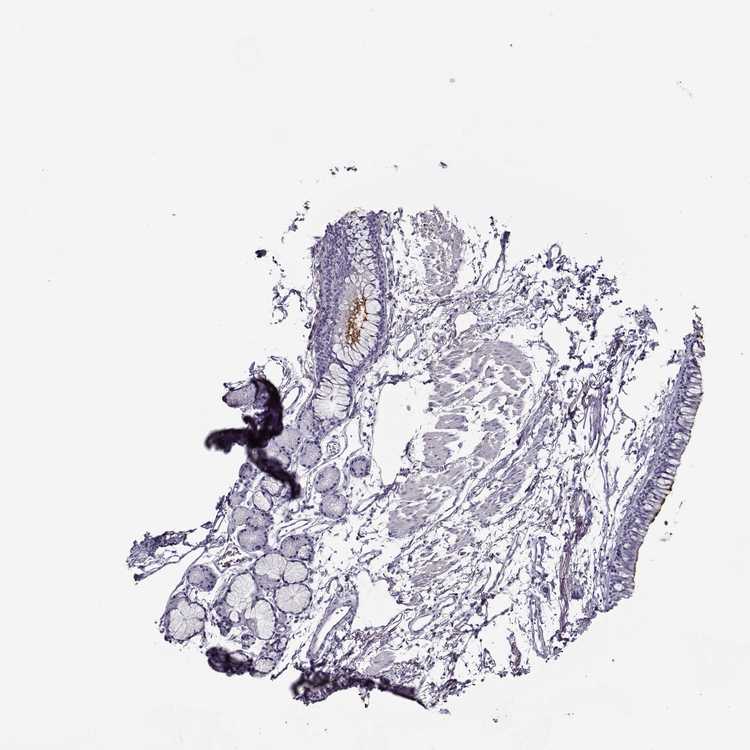

SOFT TISSUE 1 - Antibody stainingi

Antibody staining in the annotated cell types in the current human tissue is reported as not detected, low, medium, or high, based on conventional immunohistochemistry profiling in selected tissues. This score is based on the combination of the staining intensity and fraction of stained cells.

Each image is clickable and will lead to virtual microscopy that enables deeper exploration of all samples and also displays staining intensity scores, fraction scores and subcellular localization as well as patient and tissue information for each sample.

Antibody HPA022243Antibody HPA051600

Chondrocytes Not detectedNot detected

Fibroblasts Not detectedNot detected

Peripheral nerve Not detectedNot detected

SOFT TISSUE 2 - Antibody stainingi